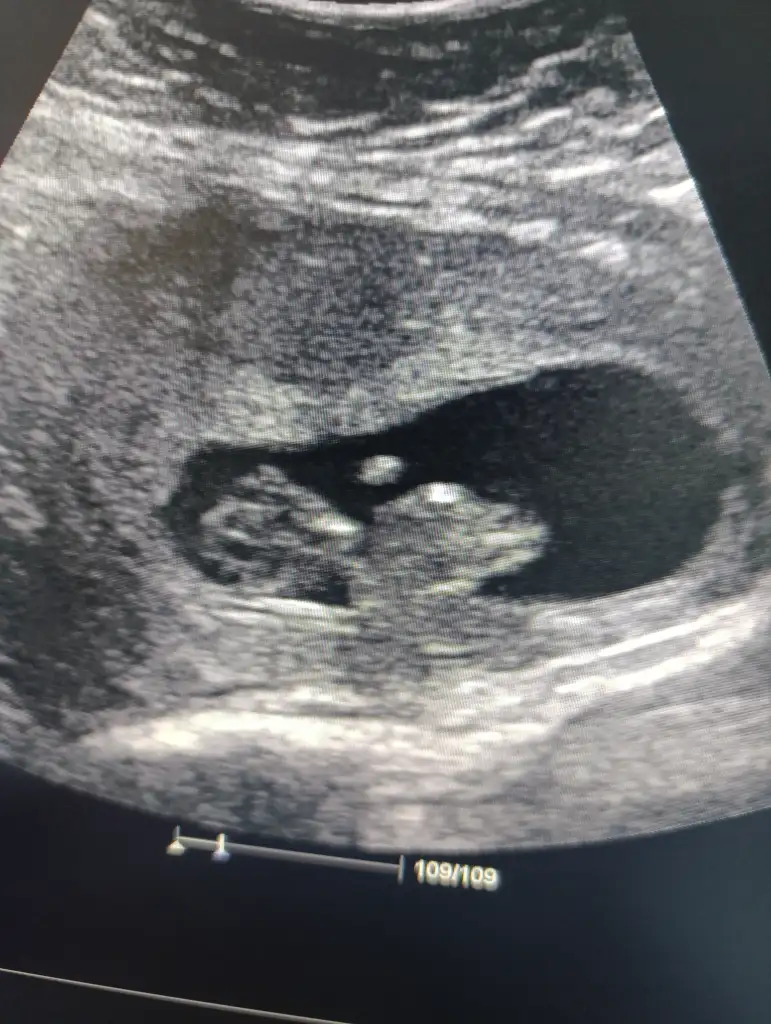

Bunada bakar mısınız rica edersemkız gibi

Bunada bakar mısınız

çok küçük ama kese kız gibiBana da yorum yapar mısınız 8 haftalık vajinal bakıldı

Ayy insallah ağzınız bal yesinçok küçük ama kese kız gibi